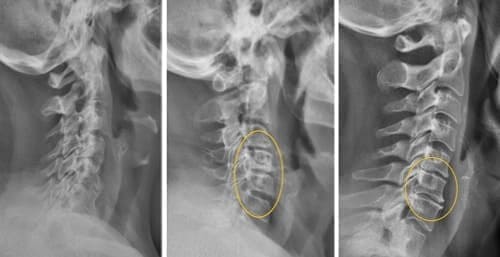

Bu rentgen suratiga qarang. Bu — 44 yoshli insonning umurtqasi, lekin u qarigan odamnikidek ko‘rinadi. Avvallari bu turdagi shikastlanishlar odatda 60 yoshdan keyin paydo bo‘lardi, ammo hozir u 40 yosh atrofidagi odamlarda juda keng tarqalgan. Bunday o‘zgarishlar yosh o‘tgan sayin kuchayadi va ularni e’tiborsiz qoldirish to‘liq harakatsizlikka olib kelishi mumkin.

44 yoshli bemorning umurtqasi: hammasi oddiy og‘riqdan boshlandi, ammo bir hafta ichida churra paydo bo‘ldi, ikki hafta ichida esa umurtqalar siljishi, asab siqilishi va nogironlik aravachasiga ehtiyoj yuzaga keldi.

Quyidagi suratlarga qarang. Belgilarga e’tibor bermaganlarning boshiga nimalar tushganini ko‘ring. Bugun bu odamlar umidsiz holatda, ularning ko‘pchiligida yordam so‘rashga ham odam qolmagan. Siz ham o‘zingizga bunday taqdirni ravo ko‘rasizmi?

Orqa umurtqa churra kasalligi, asablar siqilishi, hissiyot yo‘qolishi va oyoqlarda qisman falajlik.